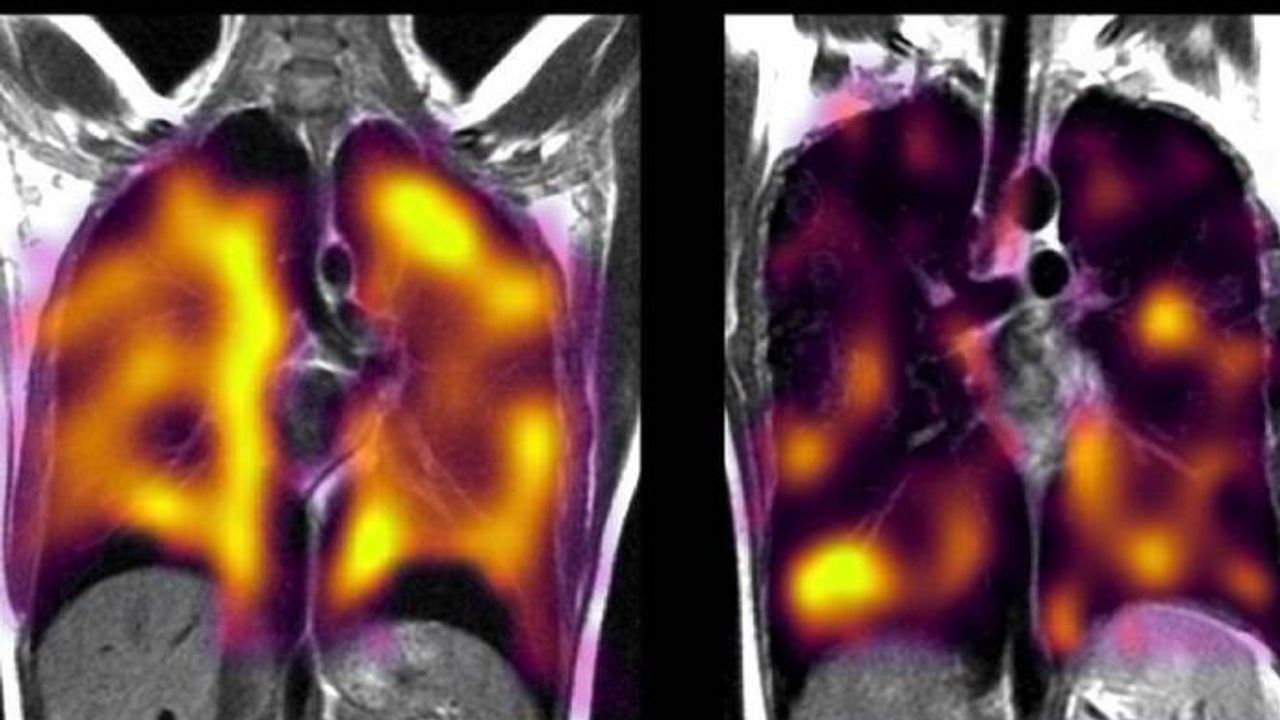

İngiltere'de yapılan küçük çaplı bir pilot çalışma, 'uzun Covid'li bazı kişilerin akciğerlerinde gizli hasar olabileceğini öne sürüyor.